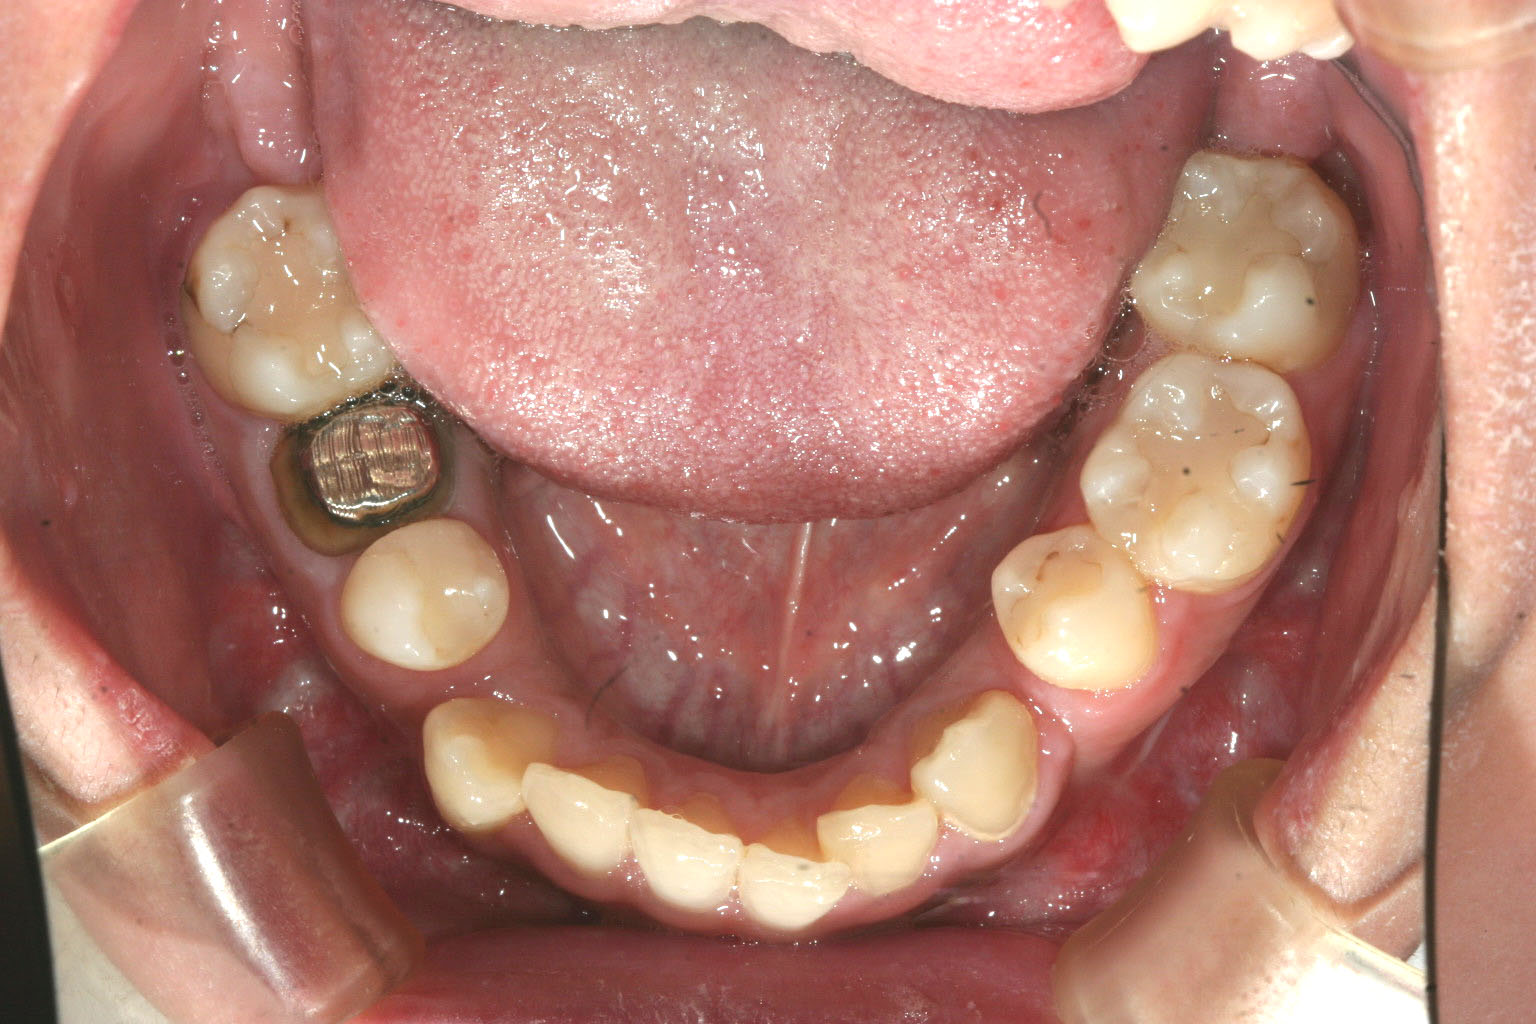

下顎には外科処置後での犬歯の後ろに少しのスペースが残っています。 もともと過度な受け口であった為下顎骨を少し削って短くしました。

下顎も外科後に残った少しのスペースを閉じるのと叢生の治療です。 綺麗に改善してます。

下顎を切断してメタルでつないであるのが見受けられます。